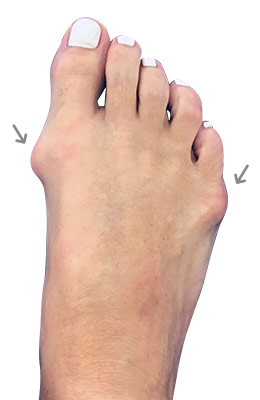

Before

Minimally Invasive Bunion Surgery featuring the CrossRoads miniBunion™ System before

After

Minimally Invasive Bunion Surgery featuring the CrossRoads miniBunion™ System after

Minimally Invasive Bunion Surgery featuring the CrossRoads miniBunion™ System

Eva is a 24-year-old female who had just began working at a job that required high fashion shoes. She was in constant pain but could not take time off work. Our miniBunion™ Minimally Invasive Bunionectomy allowed her to continue to work and be on her foot with full recovery and return to regular shoes by 6 weeks. She had an amazing range of motion, no more bunion pain, and absolutely no visible incision. After picture taken six weeks post-surgery.